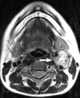

Carotid body tumor

A paraganglioma is a rare neuroendocrine neoplasm that may develop at various body sites (including the head, neck, thorax and abdomen). When the same type of tumor is found in the adrenal gland, they are referred to as a pheochromocytoma. [Source: Wikipedia ]